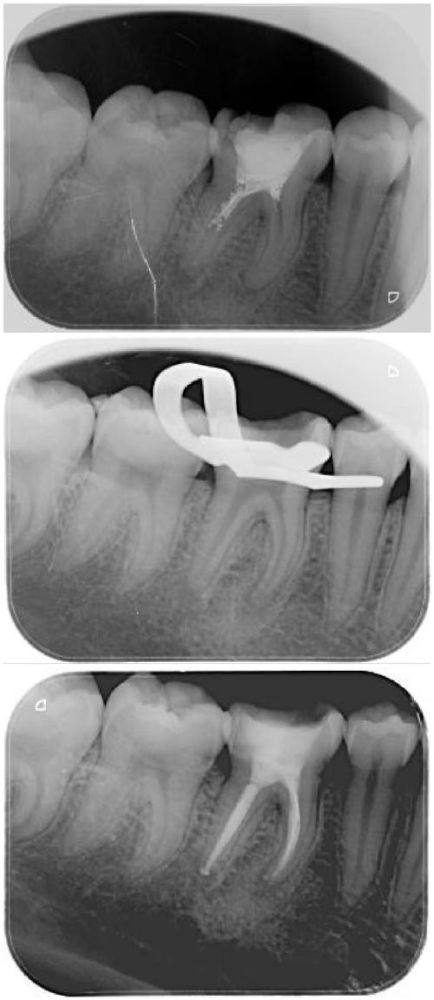

根管治疗通常不是一蹴而就的,一般需要 1 - 3 个疗程才能完成。在整个治疗环节中,杀牙神经的工作大多会在第 1 - 2 个阶段进行。这是因为牙齿内部的神经是疼痛的根源所在,只有先处理好神经,后续的治疗才能顺利开展。不过,大家也不用过于紧张,医生会根据每个人牙齿的具体情况,制定更适合的治疗方案和疗程安排。就好比盖房子,第一步得先打好基础,根管治疗中杀牙神经就是关键的基础步骤,为后续的修复和治疗创造良好的条件。

大家都特别关心根管治疗更痛苦的一步到底是什么。其实,在正规的治疗过程中,医生一般会先为患者进行局部麻醉。有了麻醉的作用,大部分患者通常不会感到剧烈的疼痛。但是,杀死神经时更痛苦的部分可能就出现在拔牙磨开、拔牙神经的时候。当医生磨开牙齿时,会触及到牙齿的敏感部位;而拔除牙神经,更是直接与疼痛源打交道。不过呢,现代的麻醉技术已经相当成熟,只要患者放松心态积极配合,那种痛苦是在可以承受范围内的。就像打针一样,虽然会有一点刺痛,但特别快就会过去啦。